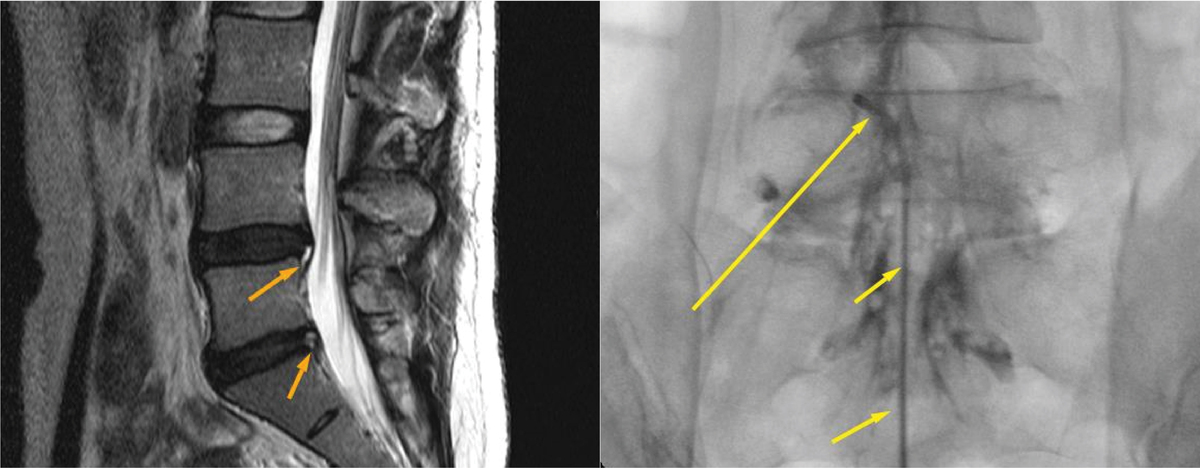

허리디스크의 정확한 진단을 위해서는 MRI 검사가 필수다. X-ray는 뼈의 형태나 골절 여부를 확인하는 데 유용하지만, 디스크와 신경의 압박 정도를 정밀하게 보기에는 한계가 있다. MRI는 척추 단면을 다양한 각도로 촬영해 디스크의 손상 정도와 신경 압박 부위를 선명하게 보여주는 검사로, 허리디스크 진단에 있어 가장 신뢰할 수 있는 방법이다. 간혹 MRI 영상과 증상이 일치하지 않는 경우에는 신경차단술을 통해 병변 부위를 확인하기도 한다.

신경차단술은 영상장치(C-arm)를 보며 통증의 원인이 되는 신경 주위에 약물을 주입해 염증과 부종을 가라앉히는 치료법이다. 통증의 원인을 직접 차단해 신경의 과민 반응을 완화하고, 시술 시간은 20분 내외로 짧으며 국소마취로 진행되어 고령자나 내과 질환자도 부담 없이 받을 수 있다.